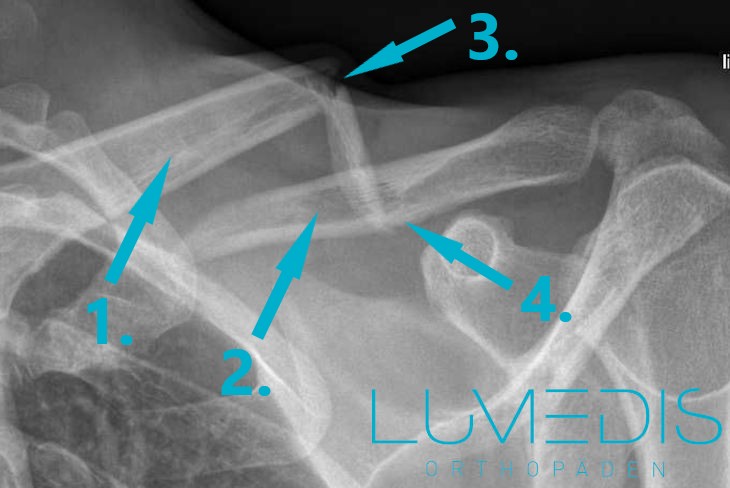

Schlüsselbeinbruch mit zwei freien Knochenfragmenten

Röntgenbild eines gebrochenen Schlüsselbeins (Dreifragmentfraktur)